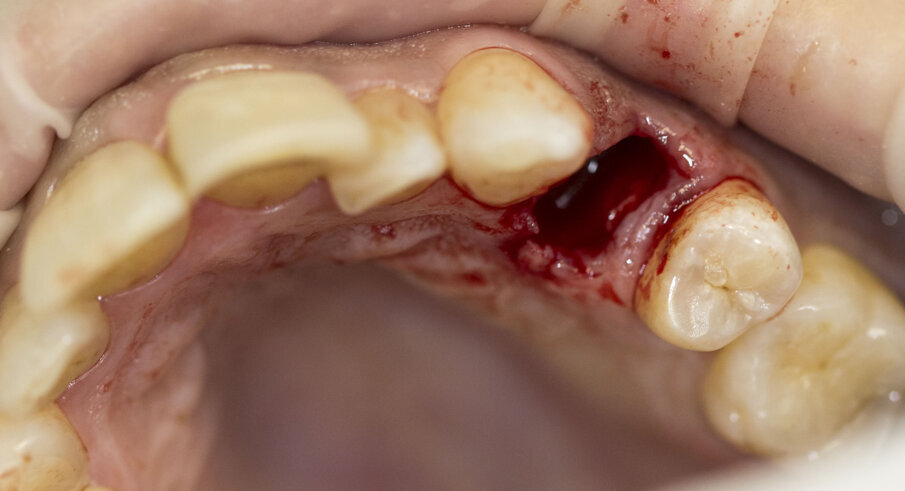

Fig. 4 - Estrazione del dente 2.4.

Fig. 5 - Posizionamento del biomateriale (cono R.T.R., Septodont) nell’alveolo.

Fig. 6 - Biomateriale in situ.